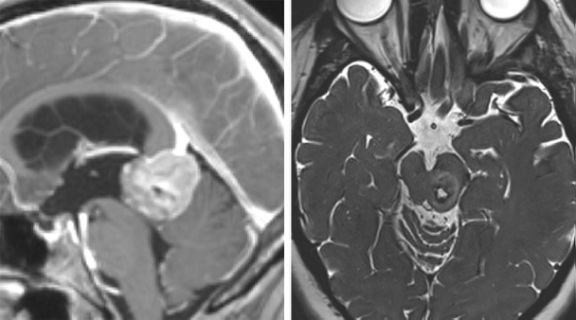

图2. 松果体区(左图)及中脑后外侧(右图)大型病变可以很容易通过小脑上入路显露。